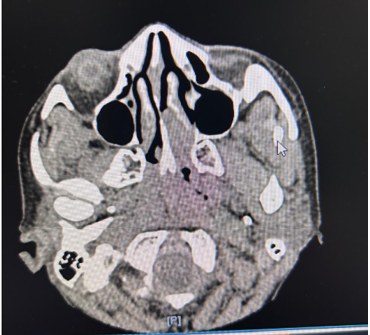

Cross-sectional CT imaging of the paranasal sinuses showed a soft tissue density lesion in the left nasal cavity centered in the middle meatus and olfactory cleft, without bony erosion or extension into the cribriform plate or orbit (Figure 1). Microscopically, the tumour showed small round blue cells with salt-and-pepper chromatin and Homer Wright pseudo-rosettes. Immunohistochemistry was positive for neuroendocrine markers (synaptophysin, chromogranin, INSM1) and negative for cytokeratin and S100, distinguishing it from sinonasal undifferentiated carcinoma or melanoma.

Figure 1.  CT scan of paranasal sinuses depicting a well-defined mass in the superior left nasal cavity abutting but not breaching the cribriform plate, with no intracranial extension.